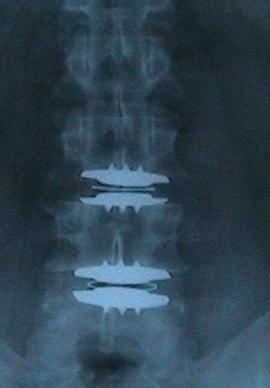

BEFORE Oct 14, 2004 -2 Published June 21, 2016 at 270 × 388 in BEFORE Oct 14, 2004 -2 ← Previous / Next →